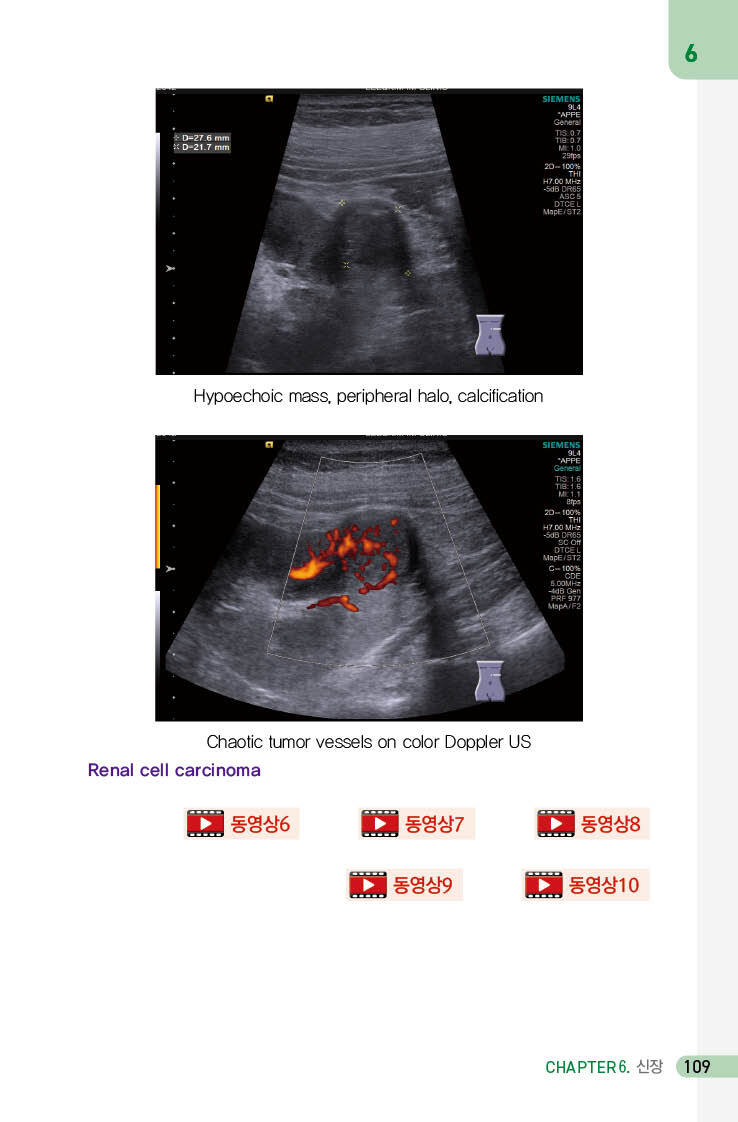

신장(세포)암 108